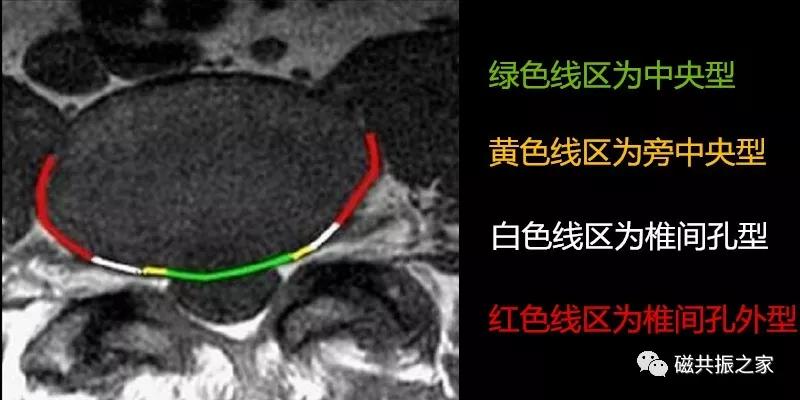

椎间盘突出:当纤维环的完整性受到破坏时,在水平方向的应力作用下,椎间盘向后或侧后突出,对于的硬膜囊、神经根及脊髓受压。

95%的椎间盘突出为中央型或旁中央型,5%的椎间盘突出为椎间孔型和椎间孔外型(图片来自网络),拓展阅读椎间盘突出表现。